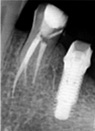

В нашей практике метод вертикальной конденсации показывает высокую клиническую надёжность, позволяет добиться рентгенологически равномерного заполнения корневых каналов зуба. В случае лечения с применением вертикальной конденсации практически исключены такие осложнения, как перепломбировка или недопломбировка до апикального отверстия.